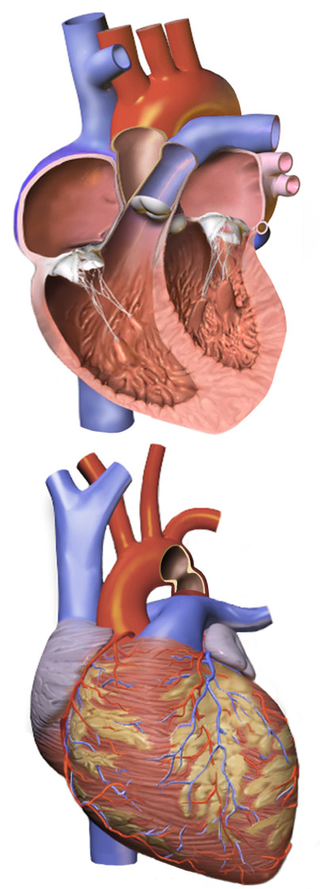

A ventricular septal defect is a flaw in the wall that separates the right and left ventricles, or septum.

An atrial septal defect (ASD) is a hole in the wall that separates the right and left atria.

Tetralogy of Fallot (ToF) is a congenital cardiovascular anomaly that includes:

- Right ventricular outflow tract stenosis

- Right ventricular hypertrophy

- Ventricular septal defect (VSD)

- An overriding aorta

Transposition of the great vessels is characterized by the aorta and pulmonary artery emerging from the right and left ventricles, respectively.

Truncus arteriosus is characterized by the emergence of a single, sizable vessel from both ventricles.

Tricuspid atresia is due to failure of the orifice of the tricuspid valve to form.

In tricuspid atresia a hypoplastic right ventricle is present.